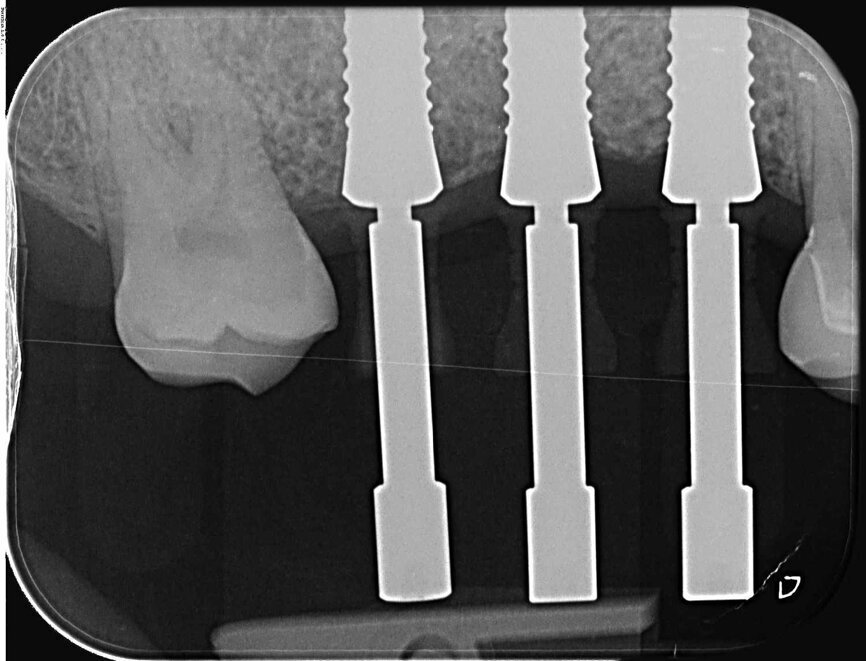

Fig. 17 : Radiographie de contrôle postopératoire.

Fig. 20 : Radiographie de contrôle.

Fig. 25 : Radiographie de contrôle après l’insertion de la prothèse définitive. Il y a lieu de remarquer le défaut intra-osseux régénéré du côté mésial de la dent 18.

Durant les visites de suivi, une et six semaines après l’insertion des restaurations implantaires tout-céramique, le tissu mou s’est avéré stable et sans irritation. La radiographie de contrôle a clairement montré la bonne ostéo-intégration des implants en céramique et la régénération du défaut osseux parodontal du côté mésial de la dent 18 (Fig. 25). Le patient s’est montré très satisfait de la réhabilitation globale de ses dents.